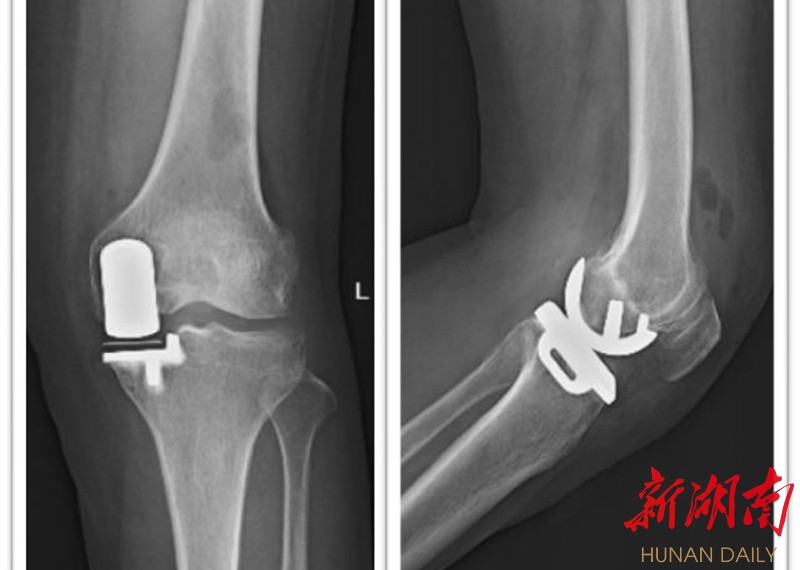

术后膝关节正侧位片